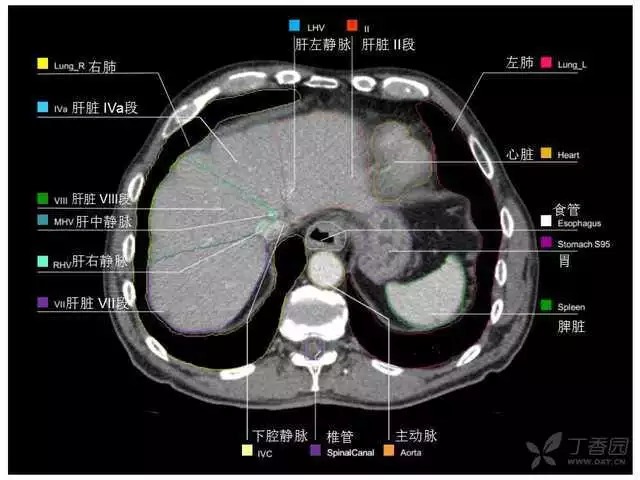

腹部肝脏高清CT断层的图谱

全腹部高清CT图谱,淋巴结彩色图谱,血管解剖图谱大汇总!

超声肝脏分叶及分段

肝脏分段和基本解剖学标志